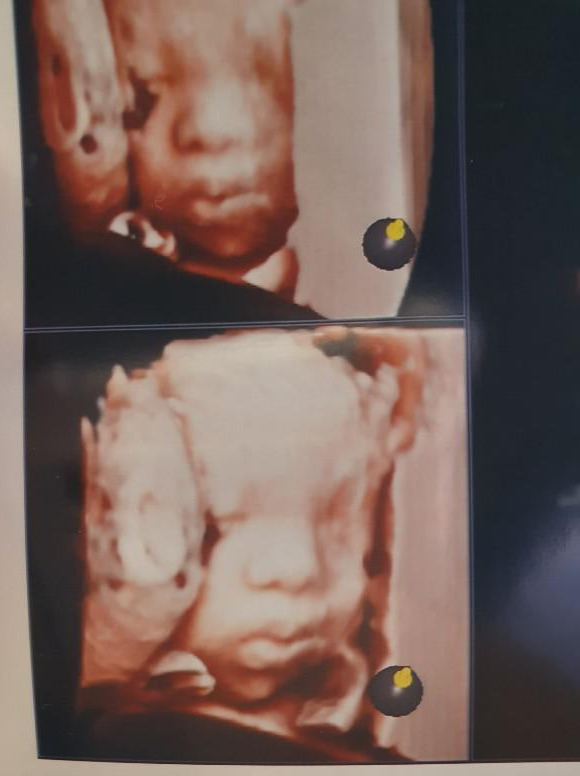

그러던 중 아내의 30주 초음파 검사를 함께 가게 되었는데요. 그때 마주한 찰떡이의 모습에 저의 마음이 더욱 단단해지는 것을 느꼈어요

KakaoTalk_20201024_084242027.jpg

찰떡아 안녕, 하품은 왜 하는거니?